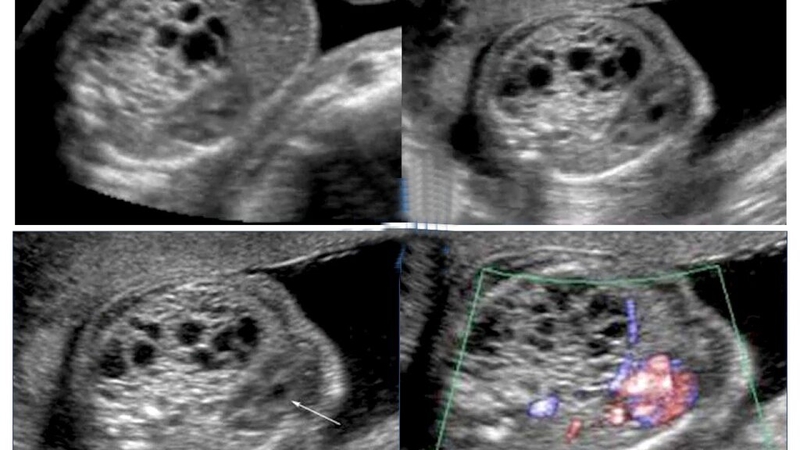

Rau bina có một nguồn axit folic dồi dào, mà axit folic là một chất rất quan trọng trong việc hình thành ống thần kinh của thai ở 3 tháng đầu của thai kỳ. Ngoài ra, việc ăn rau bina bổ sung axit folic còn giúp ngăn ngừa dị tật có thể gặp như tật hở hàm ếch, tật sứt môi… Không chỉ vậy, axit folic còn hỗ trợ cho sự phát triển của não bộ và cột sống của thai nhi, làm giảm nguy cơ sinh non của bà bầu.